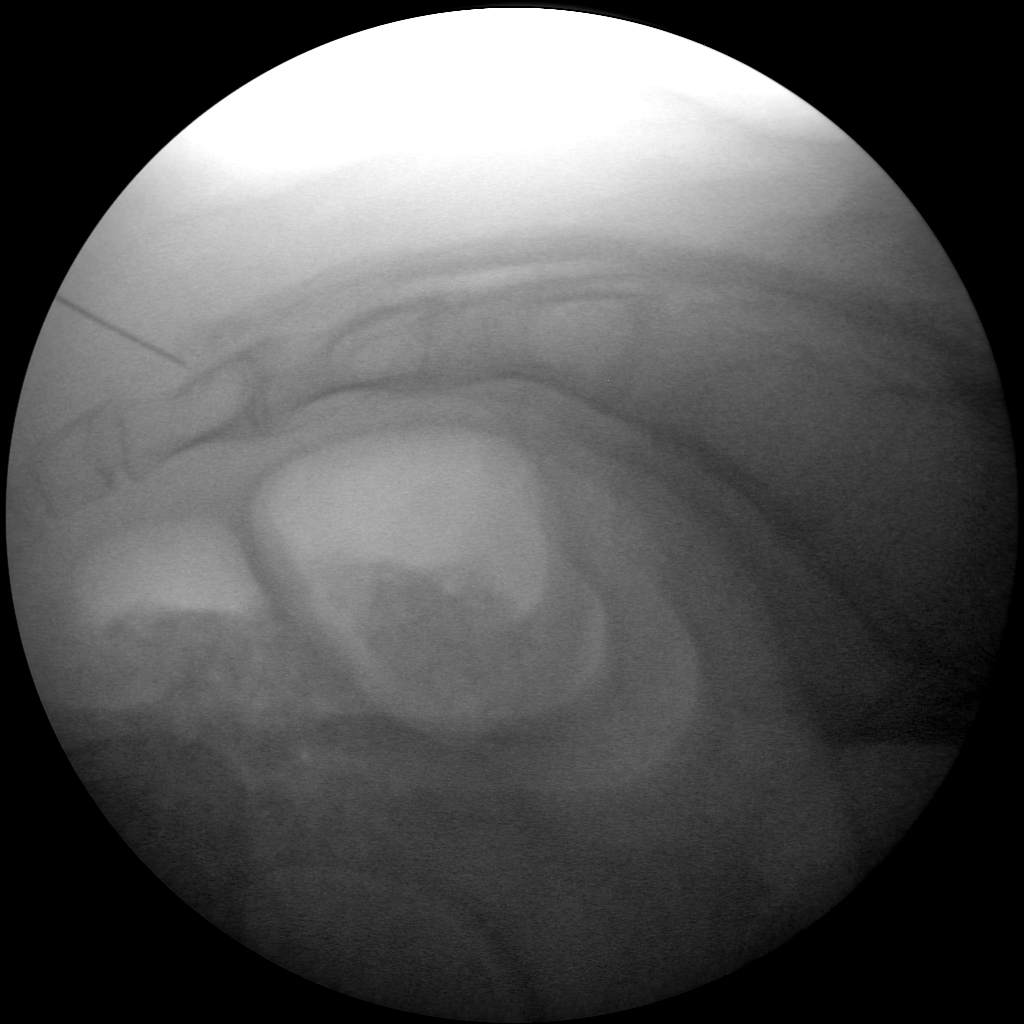

Skan-C proves highly effective in performing joint injections, a procedure commonly used to administer pain-relieving medication directly into the affected joints, such as the knee, shoulder, or hip.

Skan-C is an invaluable tool for performing Radiofrequency Ablation (RFA), a procedure that uses heat to disable nerves responsible for transmitting pain signals. Skan-C's advanced imaging capabilities facilitate precise localization of the target nerves, guiding the placement of the RFA needle electrode accurately.